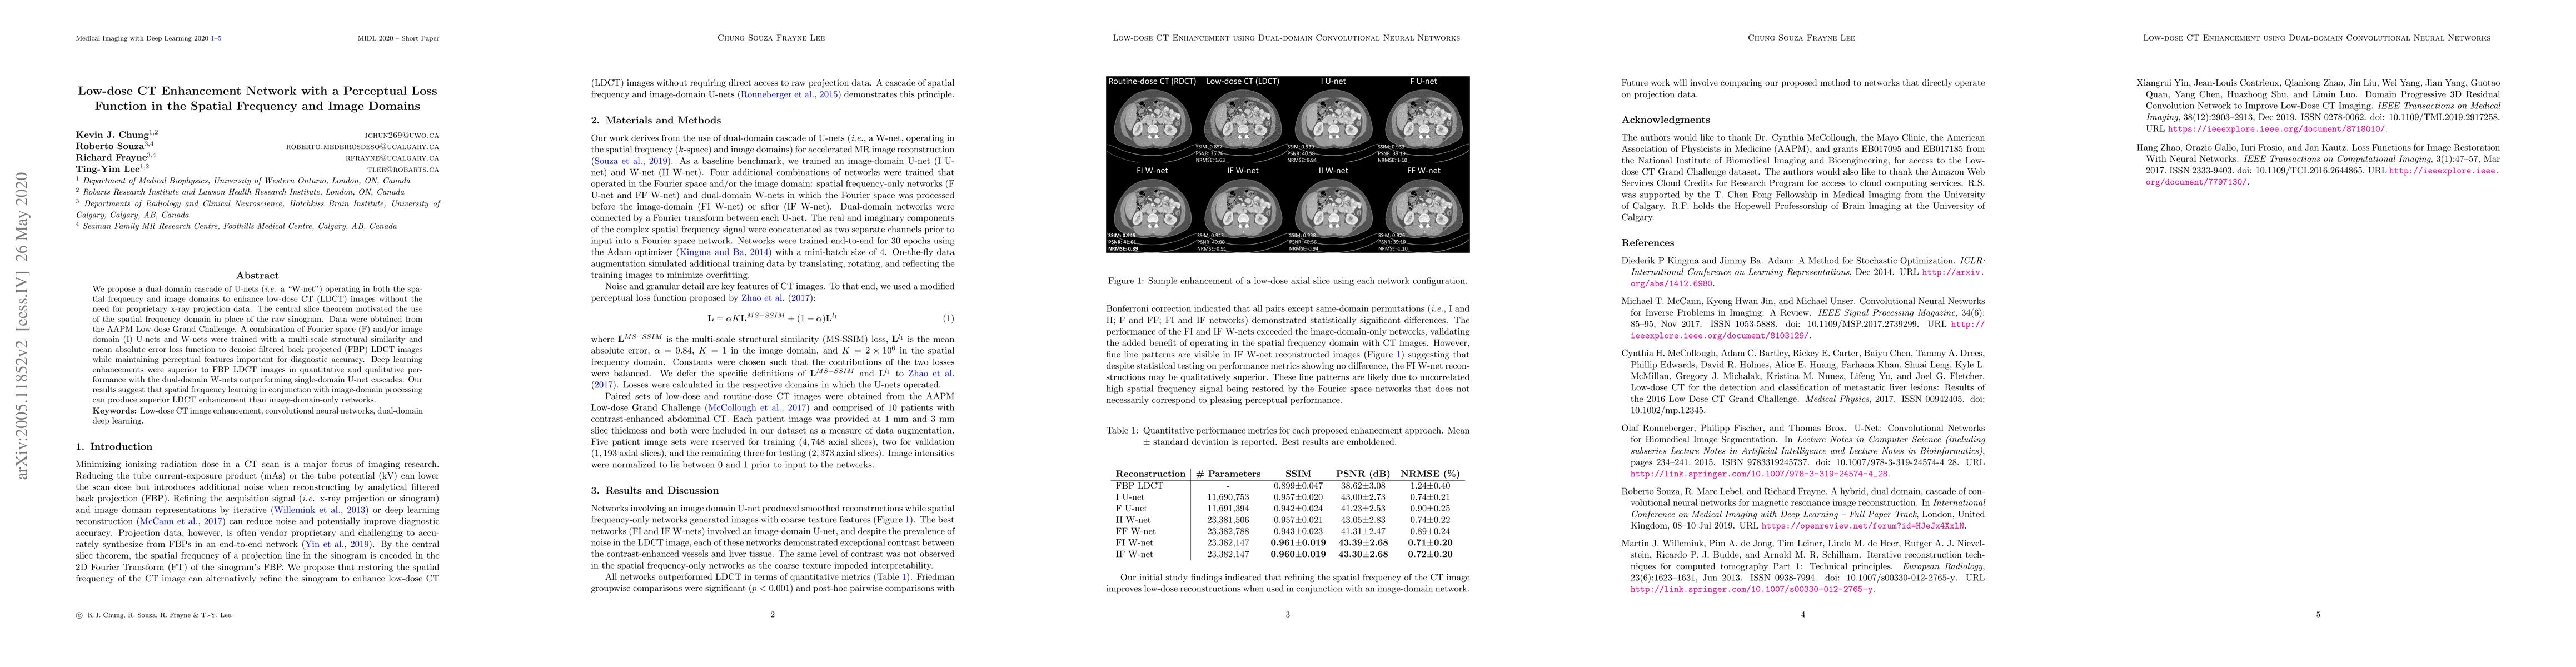

We propose a dual-domain cascade of U-nets (i.e. a "W-net") operating in both the spatial frequency and image domains to enhance low-dose CT (LDCT) images without the need for proprietary x-ray projection data. The central slice theorem motivated the use of the spatial frequency domain in place of the raw sinogram. Data were obtained from the AAPM Low-dose Grand Challenge. A combination of Fourier space (F) and/or image domain (I) U-nets and W-nets were trained with a multi-scale structural similarity and mean absolute error loss function to denoise filtered back projected (FBP) LDCT images while maintaining perceptual features important for diagnostic accuracy. Deep learning enhancements were superior to FBP LDCT images in quantitative and qualitative performance with the dual-domain W-nets outperforming single-domain U-net cascades. Our results suggest that spatial frequency learning in conjunction with image-domain processing can produce superior LDCT enhancement than image-domain-only networks.